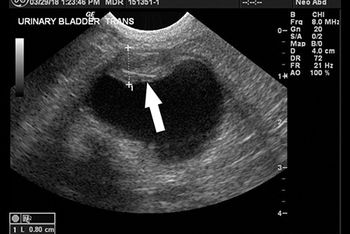

An intervention to remove urinary stones didn't alleviate this bichon frises's stranguria. See if you can spot the cause in this ultrasonogram.

Examine the ultrasonograms, study the exam findings, and see if you can name the cause in this feline patient with hematuria and recurrent UTIs.